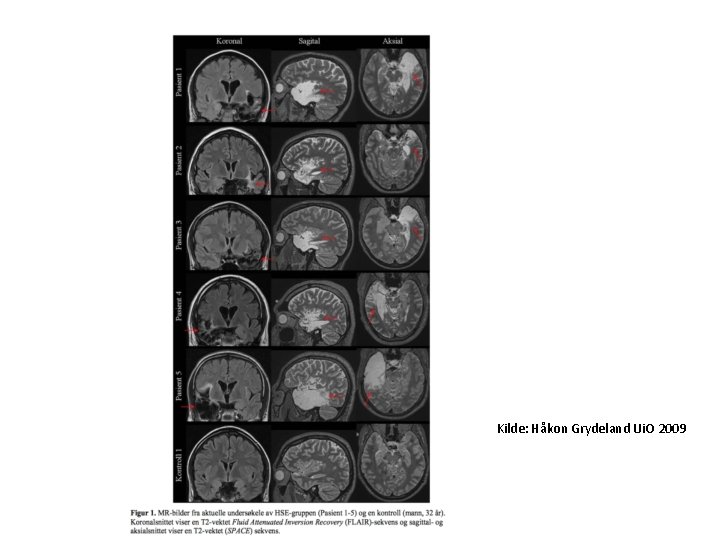

Supplerende undersøkelser • • CSF: Mål trykk. Celler: Økt, oftest <250/µL, overveiende mononukleære, men helt initialt kan det være overvekt av polymorfnukleære. Protein: Moderat økt, oftest <1. 5 g/L. Glukose: Normalt, dvs >50% av blodglukose (målt samtidig). PCR: Herpes simplex virus type 1 og 2, varicella zoster, enterovirus (høy sensitivitet (96– 98%) og spesifisitet (95– 99%) ved herpesencefalitt). PCR herpes forblir positiv minst 5 dager etter behandlingsstart, men kan være negativ i tidlig sykdomsfase. Ved negativ PCR i første prøve; ny prøve etter 3 -7 døgn. Borrelia antistoff. Blodprøver: Leukocytter med diff, CRP, trombocytter, Na, borrelia antistoff, TBE (evt andre vira) antistoff. MR caput: Ca 90% med herpesencefalitt har forandringer i en eller begge temporallapper. EEG kan være nyttig. Ved herpes simplex encefalitt har >80% høyamplitydige trifasiske bølger unilateralt temporalt.

Herpes Simplex encefalitt • Symptomer og tegn – Kan utvikles over timer til flere dager. Feber, hodepine, nedsatt våkenhet, forvirring, personlighets forandring - endret adferd, hukommelsesproblemer, anfall (kramper, lukt hallusinasjoner), kvalme/oppkast. – Feber (98 %), endret mental status (90 %), meningisme (55 %), hemiparese (33 %), afasi (28 %), hemianopsi (21 %) • • • CSF : Pleocytose (10 -2000 celler). Normalt celletall kan forekomme (< 5%). Protein moderat forhøyet. Glukose normal hos 90%. Høyt antall erytrocytter og xhantochromi kan forekomme. PCR er beste metode for påvisning av HSV - har høy sensitivitet (96– 98%) og spesifisitet (95– 99%). Forblir positiv minst 5 dager etter behandlingsstart, men kan være negativ i tidlig sykdomsfase. Ved negativ PCR i første prøve; ny prøve etter 37 døgn 1. MR caput : ca 90% har forandringer i en eller begge temporallapper, evt andre områder i hjernen/hjernestamme. Kommer ofte etter noen dager, gjenta us. EEG: patologisk hos ca 75 % - diffuse slowing, evt trifasiske bølger unilat. temporalt. CT caput : oftest normal.

Kilde: Håkon Grydeland Ui. O 2009